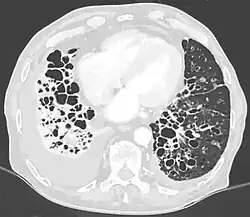

Als Bronchiektasen bezeichnet man in der Medizin irreversible sackförmige oder zylindrische Ausweitungen bzw. Erweiterungen der mittelgroßen Atemwege (Bronchien). Dieser Zustand wird auch Bronchiektasie genannt. Begleitet werden diese Ausweitungen von einer chronischen nekrös eiternden bakteriellen Infektion der Bronchialwand. Eine Erweiterung von Bronchiolen wird als Bronchiolektasie[1] bezeichnet.

- HR-CT: zystische Aufhellungen, Erweiterung der Bronchiallumina; sicherster und zuverlässigster Bronchiektasie-Nachweis